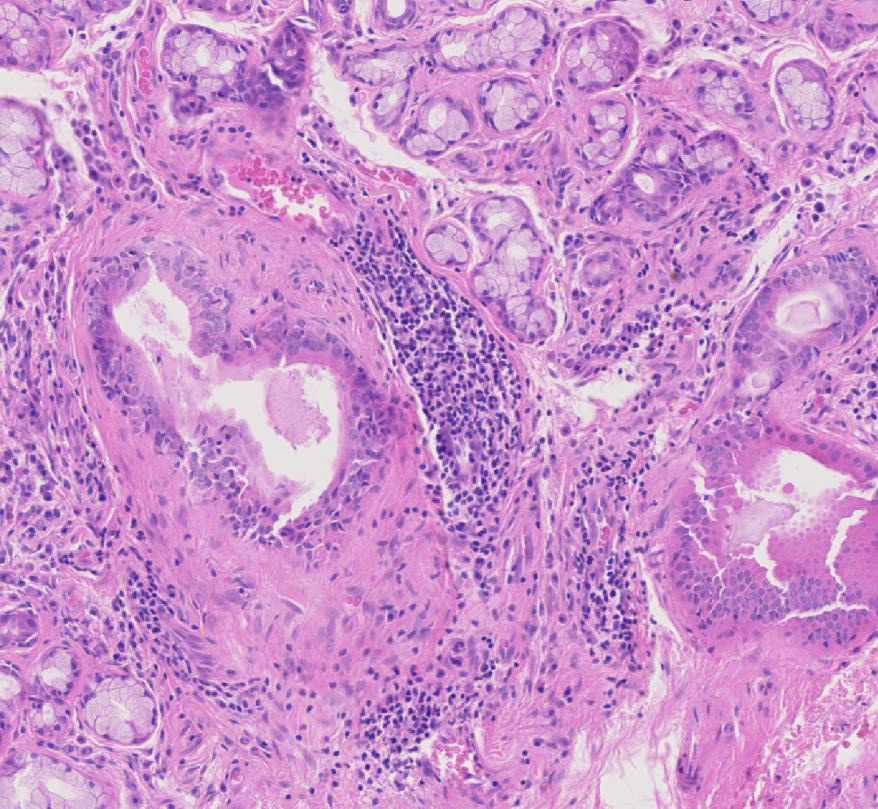

Figure 2

Haematoxylin and eosin staining of labial salivary gland biopsy with evident lymphoepithelial lesion.

Histologically, pSS is characterised by the formation of periepithelial mononuclear cell infiltrates (fig. 1). The aggregates preferentially form in the exocrine glands: salivary glands, lachrymal glands and exocrine pancreas. The histological lesions typical of SS occur in both major and minor salivary glands. Although the major salivary glands, in particular parotid glands, are often the sites of formation for the B cell lymphoma, in the majority of cases, it is not justifiable to obtain a major salivary gland biopsy owing to its inconvenience to patients and the possible complication of salivary fistula, scarring and facial nerve damage [13]. Few groups with a specific interest in SS routinely perform major salivary gland biopsy, which, however, in experienced hands, has a rather acceptable safety profile. Nonetheless, minor salivary gland biopsy can be obtained in a day-care facility with minimal invasiveness and discomfort [14]. Studies looking at the concordance of the histological lesions between the major and minor glands are reassuring, showing similar diagnostic sensitivity and specificity [15]. Nonetheless, the predominance of lymphoepithelial lesions (areas of lymphocytic infiltration of the duct that result in atrophy of the columnar ductal epithelium and proliferation of the basal epithelial cells [fig. 2]) and the detection of better-organised germinal centres in the former in the major but not minor salivary glands has to be acknowledged [16–18].